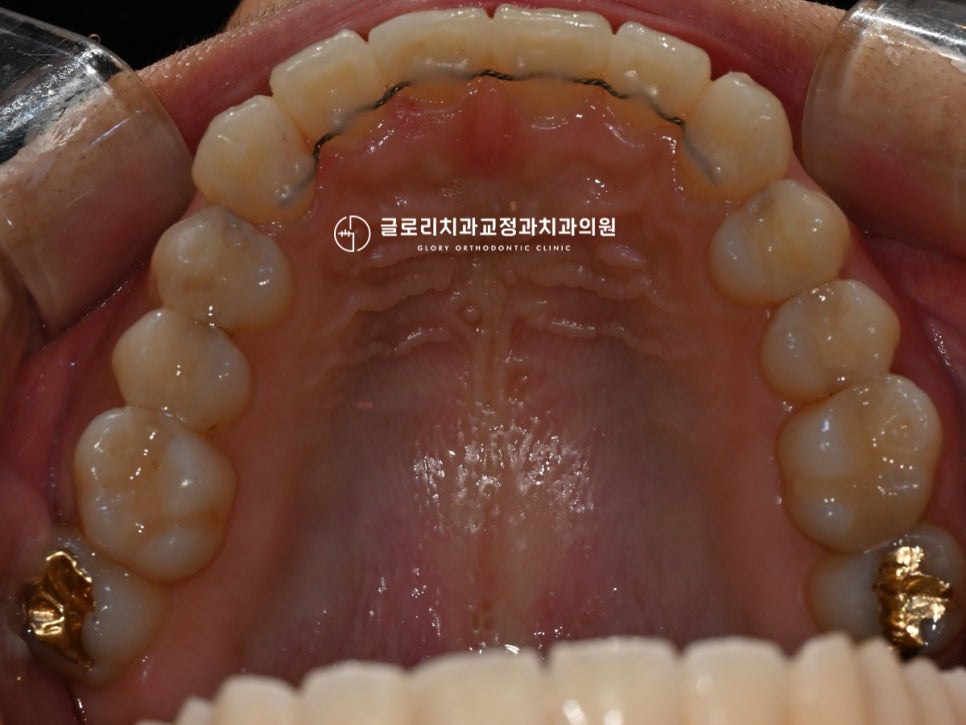

망우동치과 에서는 디지털 스캔을 이용하여

치열과 치아의 삐뚤어짐 정도, 방향 등을

정확히 파악을 했습니다.

이후 알맞은 곳에 브라켓을 부착한 후

본격적인 치아 이동을 도왔는데요.

이때 브라켓을 아무 곳에나 붙이는 것이 아니라ㅎㅎ

치아의 이동 방향 및 속도 등을 모두 고려하여

최대 이동력을 얻을 수 있는 곳에

세팅을 도와드리고 있답니다.

『악궁도 둥근 형태로 더 예뻐진 모습이죠?』